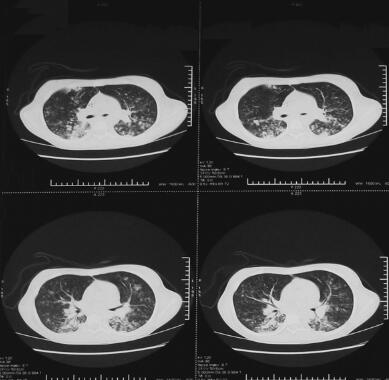

诊治经过:血常规:WBC 8.79×109/L,N 83.1%,Hb 97g/L,HCT 28%,PLT 206×109/L;血气分析:pH 7.432,PCO2 40.0mmHg,PO2 92.3mmHg,BE−2.2mmol/L,HCO3 26.4mmHg,PO2 98.3%。头颅CT:左侧海马可疑斑片状低密度影:海马变性?轻度脑萎缩?左颞极蛛网膜下腔增宽。腰穿压力185cmH2O。脑脊液常规:无色清,PandyT阴性,细胞数32/μl,白细胞数2/μl,多核细胞0/μl,单核细胞0/μl。脑脊液生化:Pro 15.0mg/dl,Cl− 130.0mmol/L,Glu 3.0mmol/L。脑脊液结眀试验(−),结核分枝杆菌抗体(−)。Touch试验:EB-VAC-IgG、CMVIgG、HSV-I-IgG均为(+);EB-VAC-IgM、CMV-IgM、HSV-I-IgM、COX-IgG、COX-IgM均为(−)。胸片提示肺部感染;胸片提示两肺纹理粗重、模糊;多次痰培养结果回报为金黄色葡萄球菌,对磺胺类、万古霉素、链霉素敏感;行肺CT检查提示双肺多发渗出性病变(图1)。

图1 6月30日肺CT:双肺渗出性病变,局部可见蜂窝状改变

葡萄球菌能产生多种毒素和酶,如溶血素、葡萄球菌激酶、凝固酶等。患者常有弛张热,成人患者发热一般不太高,但迁延多日。新生儿可为低热或无热。肺炎发展迅速,中毒症状较明显,甚至呈休克状态。可有量不多、黏稠不易咳出的脓血性痰。早期肺部病变较少,但患者可出现严重的呼吸窘迫,并有过度换气。应注意询问有无化脓性扁桃体炎或上呼吸道感染史,查体时注意是否有皮肤感染(脓疱、小疖肿、睑缘炎、甲沟炎),注意婴儿有无猩红热或麻疹样皮疹,儿童有无荨麻疹,胸部查体注意脓胸或脓气胸体征,有无肝脾肿大。进行痰、血液及胸腔穿刺液细菌培养及药敏试验可明确诊断。肺部X线检查可见小斑点阴影迅速扩大成大片状,病灶中心呈蜂窝状或肺气囊改变,可出现胸腔渗液或肺大疱。但此病临床症状与胸片所见不一致。当肺炎初起时,临床症状很重,而X线征象却很少,仅表现为肺纹理重,一侧或双侧出现小片浸润影;当临床症状已趋明显好转时,在胸片上却可见明显病变,如肺脓肿和肺大疱等。本例患者发热、痰多,但胸片表现未见明显异常,10余天后胸片出现浸润影,肺CT见渗出性病变。因患者自行要求转院,故未能追踪后期影像学变化。